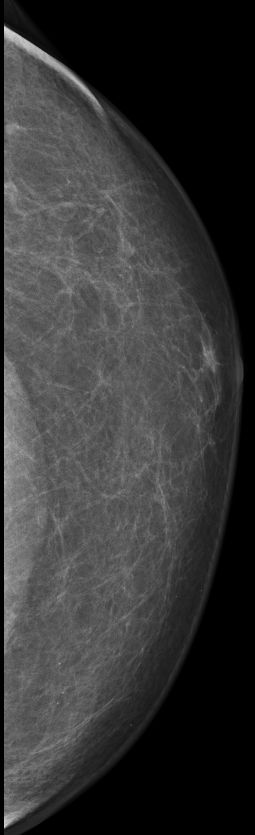

| DCIS | 80-jähriger Mann mit einem Knoten rechts retromamillär. Mammographie: Dichter Knoten mit multiplen Mikroverkalkungen unmittelbar periareolär. Histologie: papilläres DCIS, G2, 19 mm, ER: 12/12, PR: 6/12, Ki-67: 20%. Th.: Exzision, Radiatio der Mamma, TAM über 5 Jahre | ||||

rechts CC![]() |